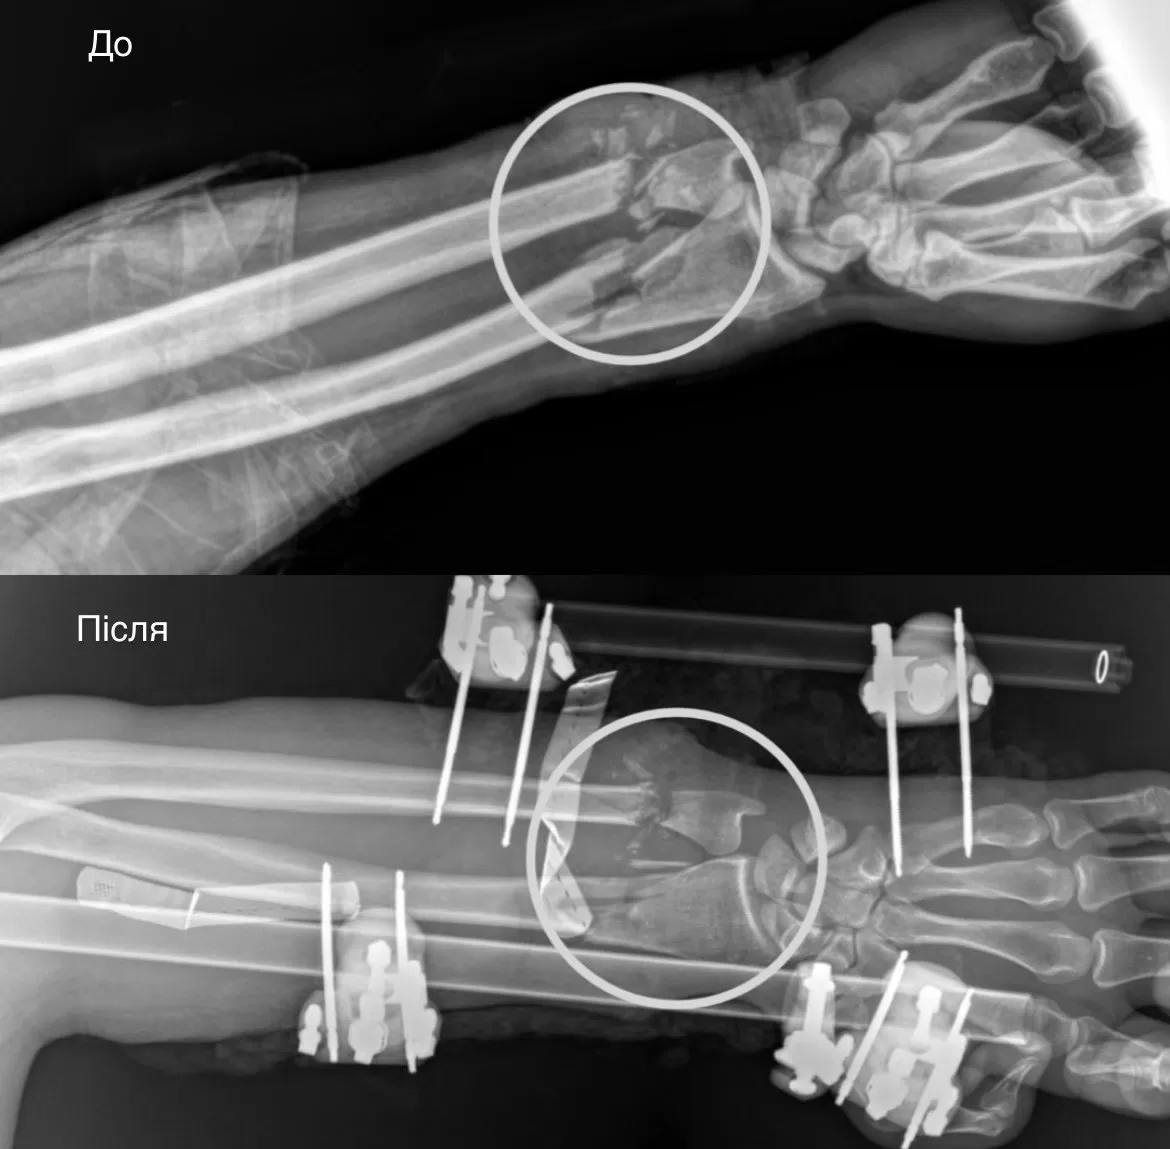

First, orthopedic traumatologists stabilized the broken bones of the forearm using an external fixation device. Then vascular surgeons restored blood supply by suturing the vessels.

In the third stage, surgeons restored the soft tissues: they sutured the tendons and muscles to restore flexion and extension functions. The nerves were prepared for further surgery, which is scheduled in a month or two. The procedure was completed with autodermoplasty—the defect was closed with the patient’s own skin.